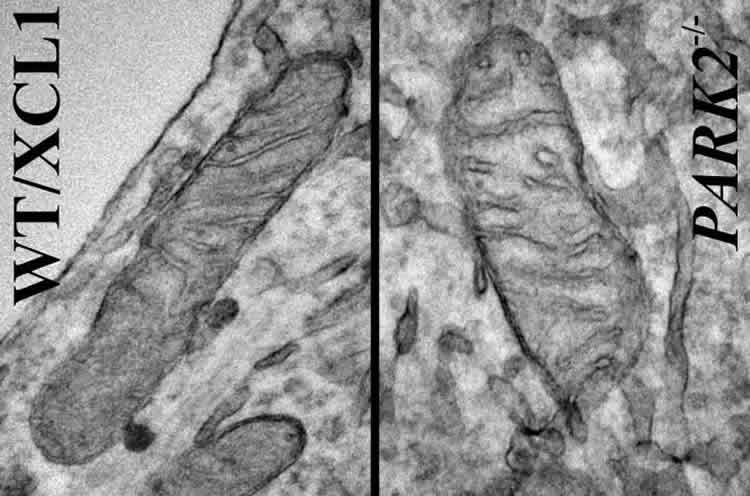

Mitochondria are energy-producing organelles found in large numbers in most cells and are necessary for life. Zeng says the Park2 mutation altered mitochondrial structure and function in dopamine producing neurons, causing them to die. Dopamine is an essential neurotransmitter which regulates movement and emotion.

The research involved making mutations in the Park2 gene in well-characterized induced pluripotent stem cell (iPSC) lines as well as generating iPSC lines from skin cells of four patients who have PD. “What we saw was extraordinary,” said Zeng. “We saw the same characteristics in the dopaminergic neurons derived from patients as well as ones derived from the lines where the mutation was introduced.”

Image Source: The image is courtesy of Akos Gerencser, PhD and is adapted from the Buck Institute for Age Research

Original Research: Full open access research for “Mitochondrial Alterations by PARKIN in Dopaminergic Neurons Using PARK2 Patient-Specific and PARK2 Knockout Isogenic iPSC Lines” by Atossa Shaltouki, Renuka Sivapatham, Ying Pei, Akos A. Gerencser, Olga Momčilović, Mahendra S. Rao, and Xianmin Zeng in Stem Cell Reports. Published online April 2 2015 doi:10.1016/j.stemcr.2015.02.019